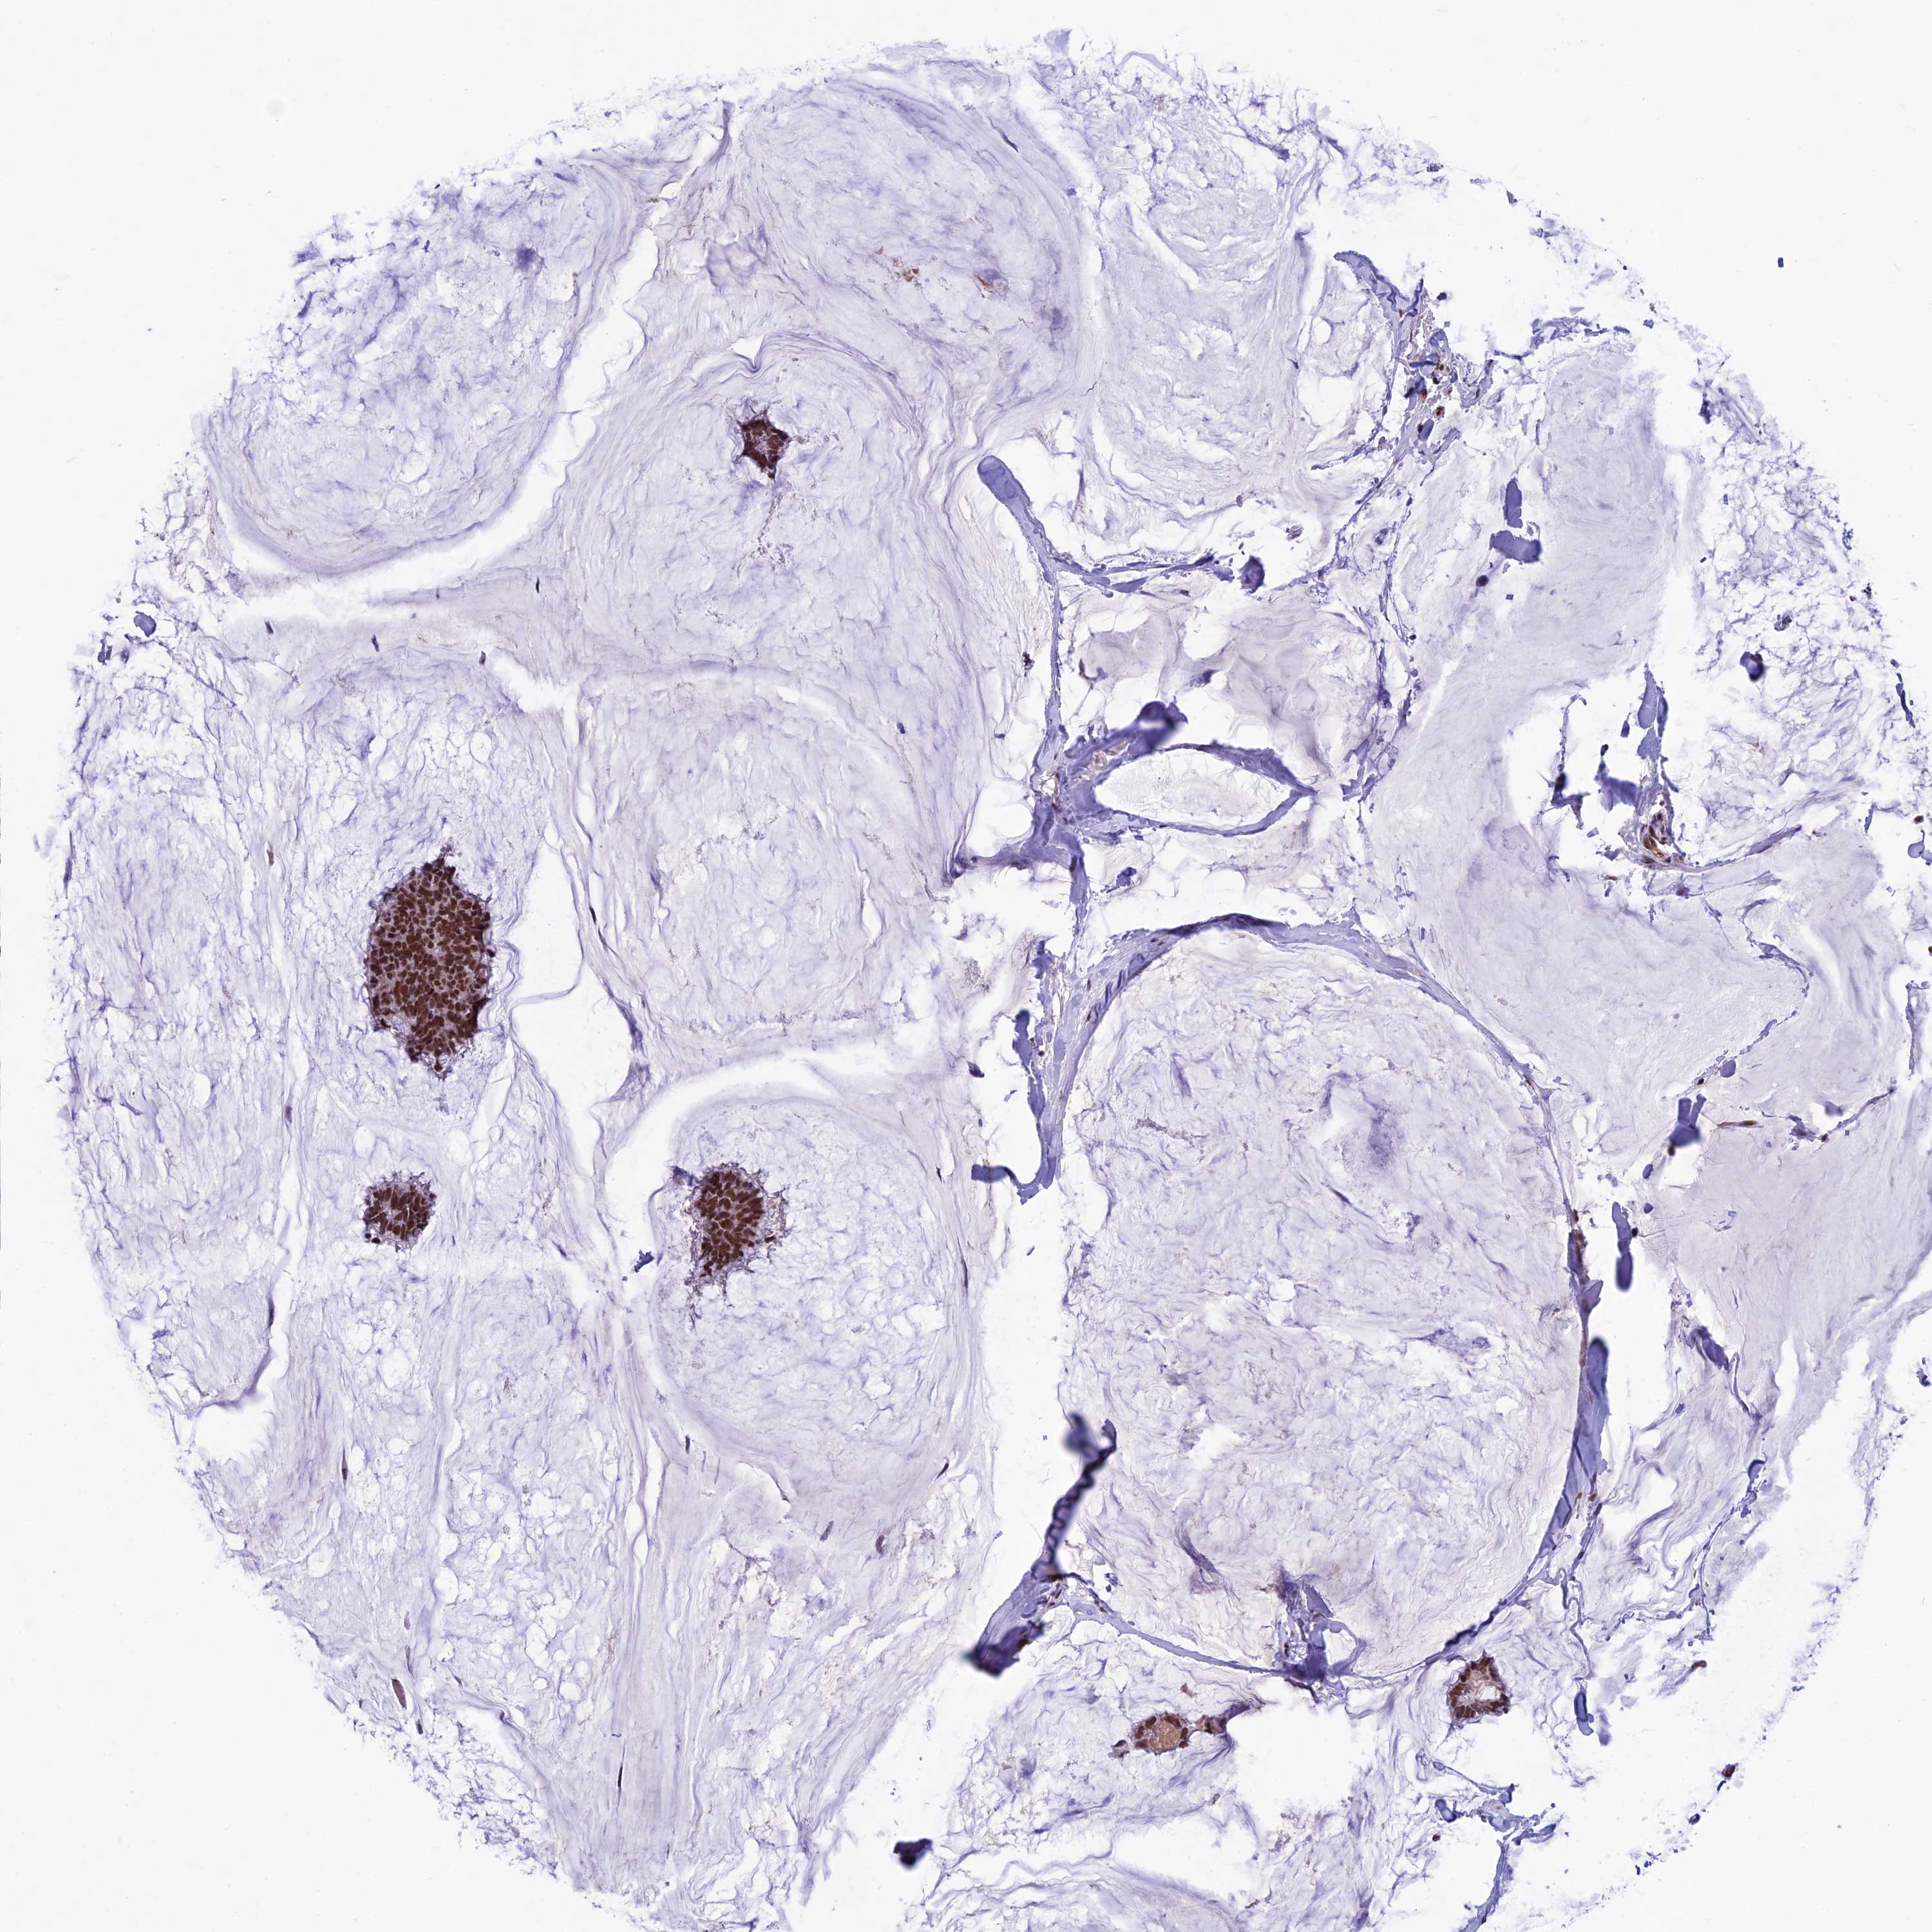

CANCER BREAST CANCER Show tissue menu

BRCA TCGA BRCA VALIDATION PROTEIN EXPRESSION